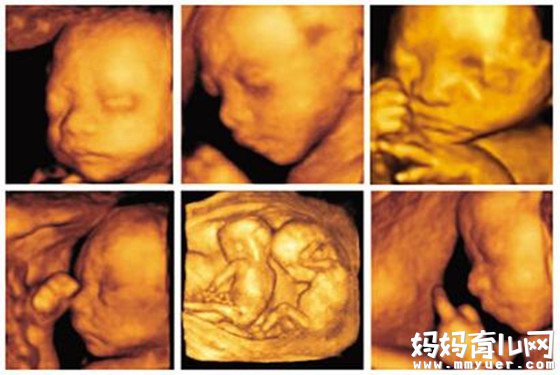

四维彩超是超声检查的一种,除了一般彩超的功能外,还可以进行胎儿头面部立体成像,可清晰地显示眼、鼻、口、下颔等状态,可协助医生直接对胎儿先天畸形进行诊断,包括表面畸形、内脏畸形和头面部畸形,能确定胎儿在子宫中的精确位置。此外,四维彩超还在这些功能的基础上加上时间维度参数,可以实时观察胎儿动态的活动图像。

四维彩超什么时候做最好?一般来说,怀孕24-28周是照四维彩超的最佳时间,因为胎儿24周左右正是大脑突飞猛进的发育时期,这个时期的胎儿结构已经形成,胎儿的大小以及羊水适中,在宫内的活动空间较大,胎儿骨骼回声影响比较小,图像也比较清晰。

四维超声在三维超声的基础上有了实时动态的效果,准爸爸、准妈妈可以通过屏幕亲眼目睹宝宝在妈妈肚子里运动、呼吸、吞咽、打哈欠、伸舌头等生理活动,非常直观。